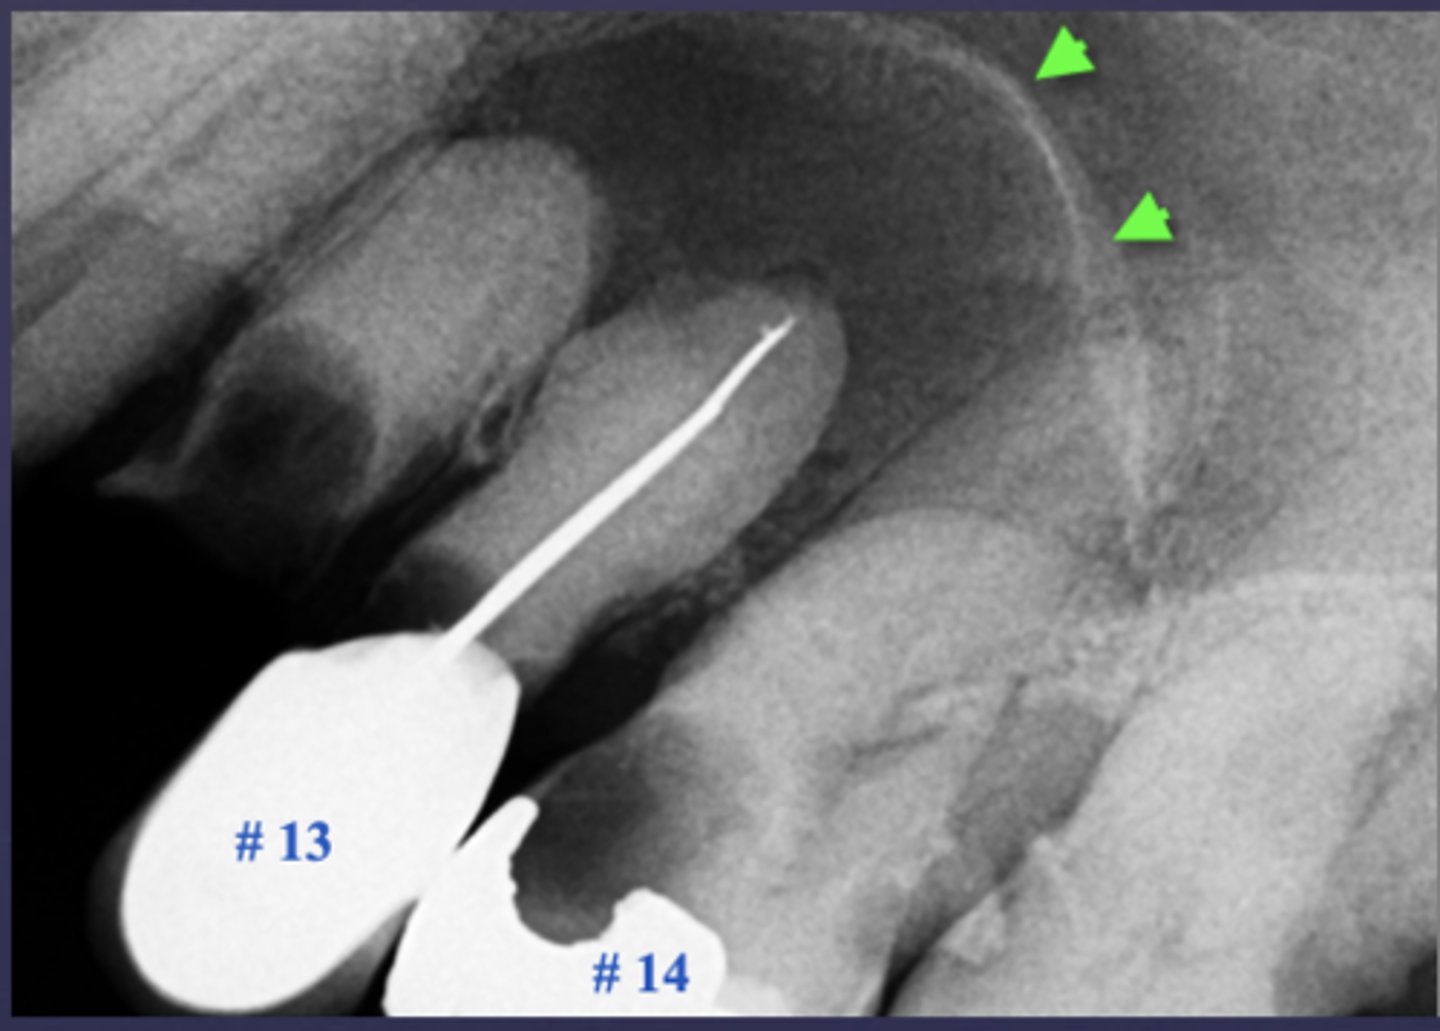

What is a key sign of periapical inflammatory disease where there is an elevation/displacement of the floor of the maxillary sinus usually affecting maxillary posterior teeth?

halo sign

What are the arrows pointing to?